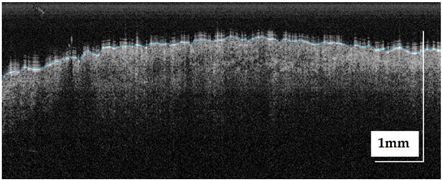

| Superficial spreading melanoma (SSM) Case 2 | Localization: right forefoot (right ankle) |

![]() | ![]() |